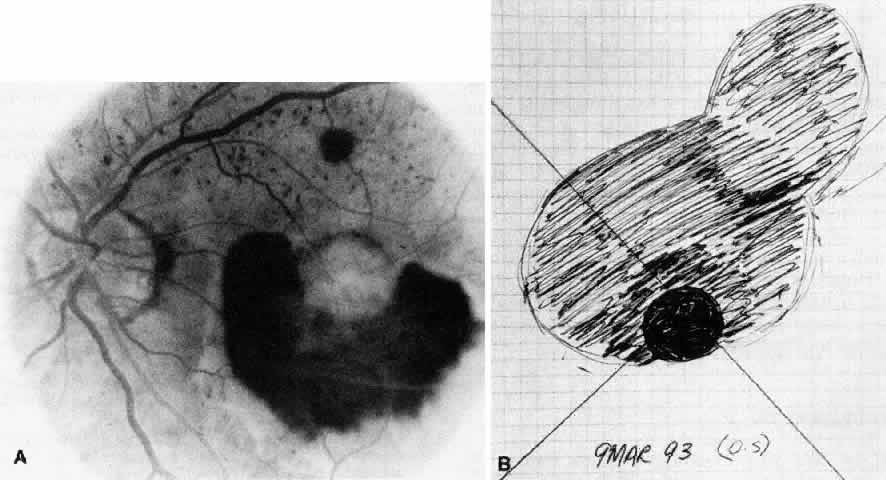

The placement of the retinotomy takes into account (1) the exact location of the membrane under the fovea; (2) the presence of presumed adhesions between the neurosensory retina and underlying tissue (previous photocoagulation scars and/or evidence of pigment migration into neurosensory retina or retinochoroidal vascular anastomoses); (3) the dimensions of the subretinal instruments (specifically the length of the angled instrument tips that determines how far away from the fovea the retinotomy can be made and still allow the tips to reach the membrane); and (4) the topographic anatomy of the neurosensory retina and nerve fiber layer. (A retinotomy made temporally in the macula disrupts less nerve fibers than does a retinotomy made nasally or superiorly that risks the creation of an arcuate visual field defect or reduced central acuity secondary to the interruption of the papillomacular bundle.) In most cases, these factors dictate a straight temporal or slightly superotemporal location for the retinotomy. However, the surgeon may choose to create a retinotomy superonasal to the fovea. With newer 33- and 36-gauge instruments, the retinotomies are small enough that no significant damage to the papillomacular bundle occurs. This approach may allow the surgeon to use his or her dominant hand for subretinal manipulation.

Besides being in the most advantageous location, the retinotomy should be as small as possible. Initially, we lightly diathermized the surface of the retina and then used the myringotomy blade to tease open a small hole through which an angled infusion needle was introduced.15 At the suggestion of Lambert and co-workers at Emory University, we stopped using diathermy. We now use a 120° angled, sharply pointed 36-gauge subretinal pick to pierce undiathermized neurosensory retina (Fig. 2). Occasional slight retinal hemorrhage can be controlled by transiently increasing the intraocular pressure. After the tiny hole has been made, the surgeon introduces the angled 33-gauge infusion needle beneath the retina and the assistant gently infuses balanced salt solution to elevate the neurosensory retina. This is accomplished by pushing on the plunger of a syringe that is connected to the hub of the needle by a short piece of tubing. As the fluid enters the subretinal space, attention is directed to edges of laser scars and/or adhesions to the underlying membrane (Fig. 3). Excessive infusion pressure can easily tear the retina. If areas of retina remain adherent, the infusion is stopped and the tip of an angled subretinal pick is carefully passed over the anterior surface of the membrane surface to break any residual adhesions. In a similar manner, the tip of the angled subretinal pick can be used to gently separate the thinned retina from an underlying photocoagulation scar. Occasionally, horizontal subretinal scissors are necessary to cut firm adhesions. These scissors have a similar 130° bend and blades approximately 3 mm in length to allow manipulation through an eccentric retinotomy. Trauma to foveal photoreceptors from either the pick or scissors is carefully avoided. If the retina is not mobilized over the entire photocoagulation scar, separation is achieved at least far enough into the scar to allow manipulation and extraction of the membrane without tearing the adjacent retina. The sharp tip of the angled subretinal pick is used to elevate the edge of the neovascular complex from the underlying RPE (Fig. 4). Care is taken to swing the pick in a pivoting or rotating manner to stretch or enlarge the retinotomy as little as possible. This requires close attention not only to the primary site of action at the membrane but also to the instrument shaft at the retinotomy site. In the appropriate cases, the complex dislodges easily from the underlying subfoveal RPE but remains attached to the edge of a laser scar (in recurrent cases) or to the stalk of choroidal vascular ingrowth.

We use positive action horizontal forceps that are angled 130° and have tips 3.2 mm in length.15 The tips are introduced (closed) through the retinotomy, which has usually enlarged slightly during the subretinal manipulation. The objective is to place the opened blades around the stalk or the adhesion, with the membrane in front of the blades. Gentle traction with the blades held closed breaks the connection (Fig. 5). This step is performed slowly and carefully. If traction on the retina is seen, the membrane is released and further separation of the complex from neurosensory retina is accomplished. If excessive tugging and displacement of surrounding RPE is seen, then consideration is given to using the subretinal scissors to cut the stalk rather than breaking it with the forceps. In virtually every case, the membrane (and often the adjacent laser scar) can be removed in one piece. As pathologic examination has confirmed, the abundance of cohesive basement membrane material matrix surrounding occasional capillaries, creates a complex of significant tensile strength.14

When the vascular connection from the choroid is about to be severed, the intraocular pressure is raised to approximately 80 mm/Hg. Despite this precaution, minimal hemorrhage is often countered when the membrane is removed. In one early case, while attention was directed to removing the neovascular complex through the sclerotomy, a massive hemorrhage occurred beneath the retina. In two additional cases, enough blood accumulated in the subretinal space to require removal with subretinal forceps. We now maintain the intraocular pressure elevated for at least 1 minute and watch closely for any evidence of rebleeding while the pressure is slowly lowered. If more bleeding occurs, the intraocular pressure is raised again. After the implementation of these measures, significant subretinal hemorrhage has not occurred in the last 60 cases.